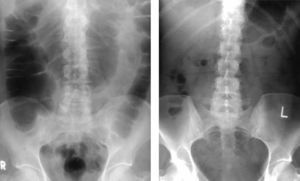

Dos estudios han medido el grado de distensión del intestino causado por la insuflación de gas durante la colonoscopia mediante radiografía simple de abdomen4,19. La radiografía se realizó una hora después de la colonoscopia y mediante una escala de 5 puntos se comparó la cantidad de gas presente tanto en el intestino delgado como en el intestino grueso entre ambos grupos. Como se puede ver en la figura 2, la cantidad de gas retenida al cabo de una hora en el intestino era menor en el grupo de pacientes en los que la colonoscopia se realizó con CO219. De hecho, hasta un 71% de los pacientes en los que la insuflación se había hecho con aire ambiente tuvieron una distensión colónica mayor de 6cm a la hora del procedimiento en comparación con solo un 4% de pacientes en los que se había utilizado CO2 para la insuflación.

Radiografía de abdomen una hora después de la colonoscopia en un paciente en el que se utilizó aire (derecha) para la insuflación y en otro paciente que se utilizó CO2 (izquierda). (Fuente: Sumanac et al.19)